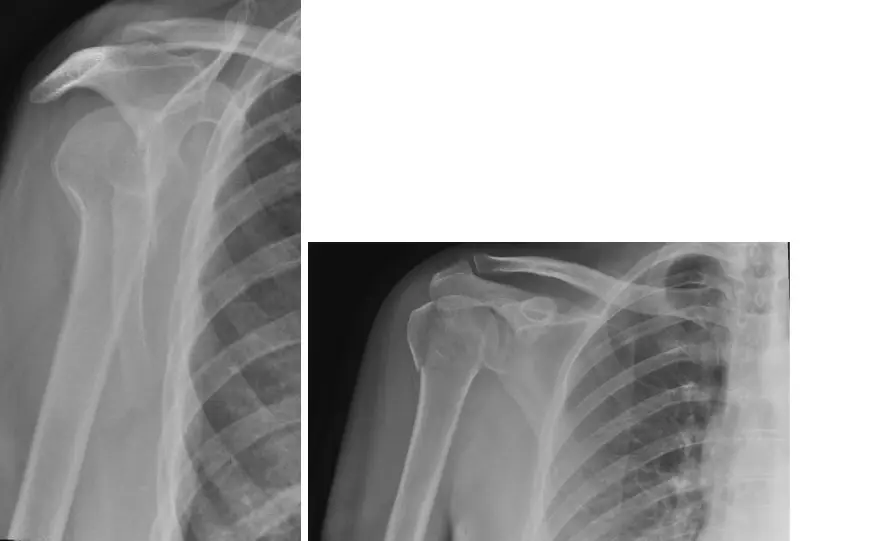

• الأشعة السينية (X-rays):

• هي أول خطوة في التصوير. يتم التقاط عدة صور من زوايا مختلفة (أمامية خلفية، Y-scapular، جانبية إبطية) لتقييم وجود الكسر ومدى تشرده الأولي.

• تساعد الأشعة السينية في الكشف عن الكسور الكبيرة والخلع المصاحب.